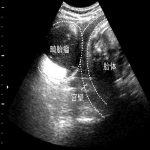

卵泡黄素化不破裂综合征(LUF) 案例:卢女士,48岁,2008年6月9日患者无明显诱因出现发热、排尿时下腹痛,在当地医院查“尿常规:红细胞++,血常规:白细胞偏高”,当地医院诊断“泌尿系感染”,行输液抗炎治疗后好转;2008年8月20日患者又出现发热、排尿时下腹痛症状,在当地医院测体温:39度,查“尿常规:红细胞++”,予安痛定肌注后仍未退热,后用高效退热药及抗炎治疗7天后好转(具体用药不详);2008年9月13日患者在当地医院查彩超示:“盆腔肿物囊实相间7cm,性质待查”;伴随左下腹胀痛,腰部偶有牵扯痛,伴大便感。FSH 0.316mIU/ml LH 0.930 ,mIU/ml ,E2 122 TESTO,84.28ng/dl,PRL 2.56ng/ml PROG 8.60 。所有肿瘤标记物均为阴性。

2008年9月20日安太医院腹腔镜探查:左卵巢囊肿,直径7cm,暗紫色,与左侧输卵管、左侧盆壁、肠管、大网膜结缔组织性粘连,操作:腹腔镜下穿刺左卵巢囊肿,抽出囊内液20ml送细胞学检查,液体为血性。松解左输卵管、卵巢与周围组织的粘连。细胞学检查结果回报为白细胞、红细胞,未见肿瘤细胞。完整剥除囊肿壁,囊肿壁为黄体组织,考虑左卵巢囊肿为黄体囊肿合并出血,3-0可吸收线连续缝合左卵巢成形。

术后诊断:卵泡黄素化不破裂综合征(LUF)

讨论:术前根据年龄和生长速度高度怀疑卵巢癌,术中确是卵泡黄素化不破裂综合征,这个现象在更年期妇女尤其明显,卵巢肿物虽然大于7cm,B超虽然提示囊实相间,仍是生理性的囊肿,实性部分就是血体。可以通过介入治疗的。